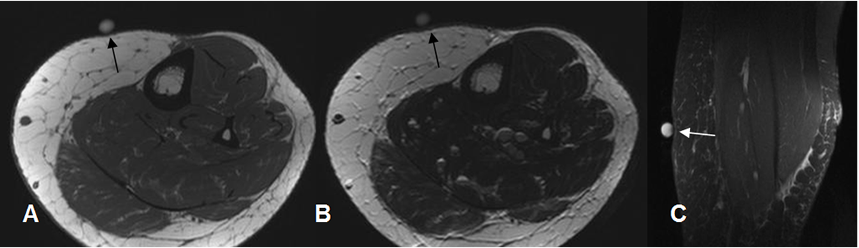

Fig 165. Fibrolipoma.

A: RM axial en T1, B: RM coronal en T1 y C: RM coronal en STIR. Lesión hiperintensa dentro del músculo biceps femoral. Su señal no es completamente hiperintensa, por algún componente fibroso y no suprime totalmente en el STIR.